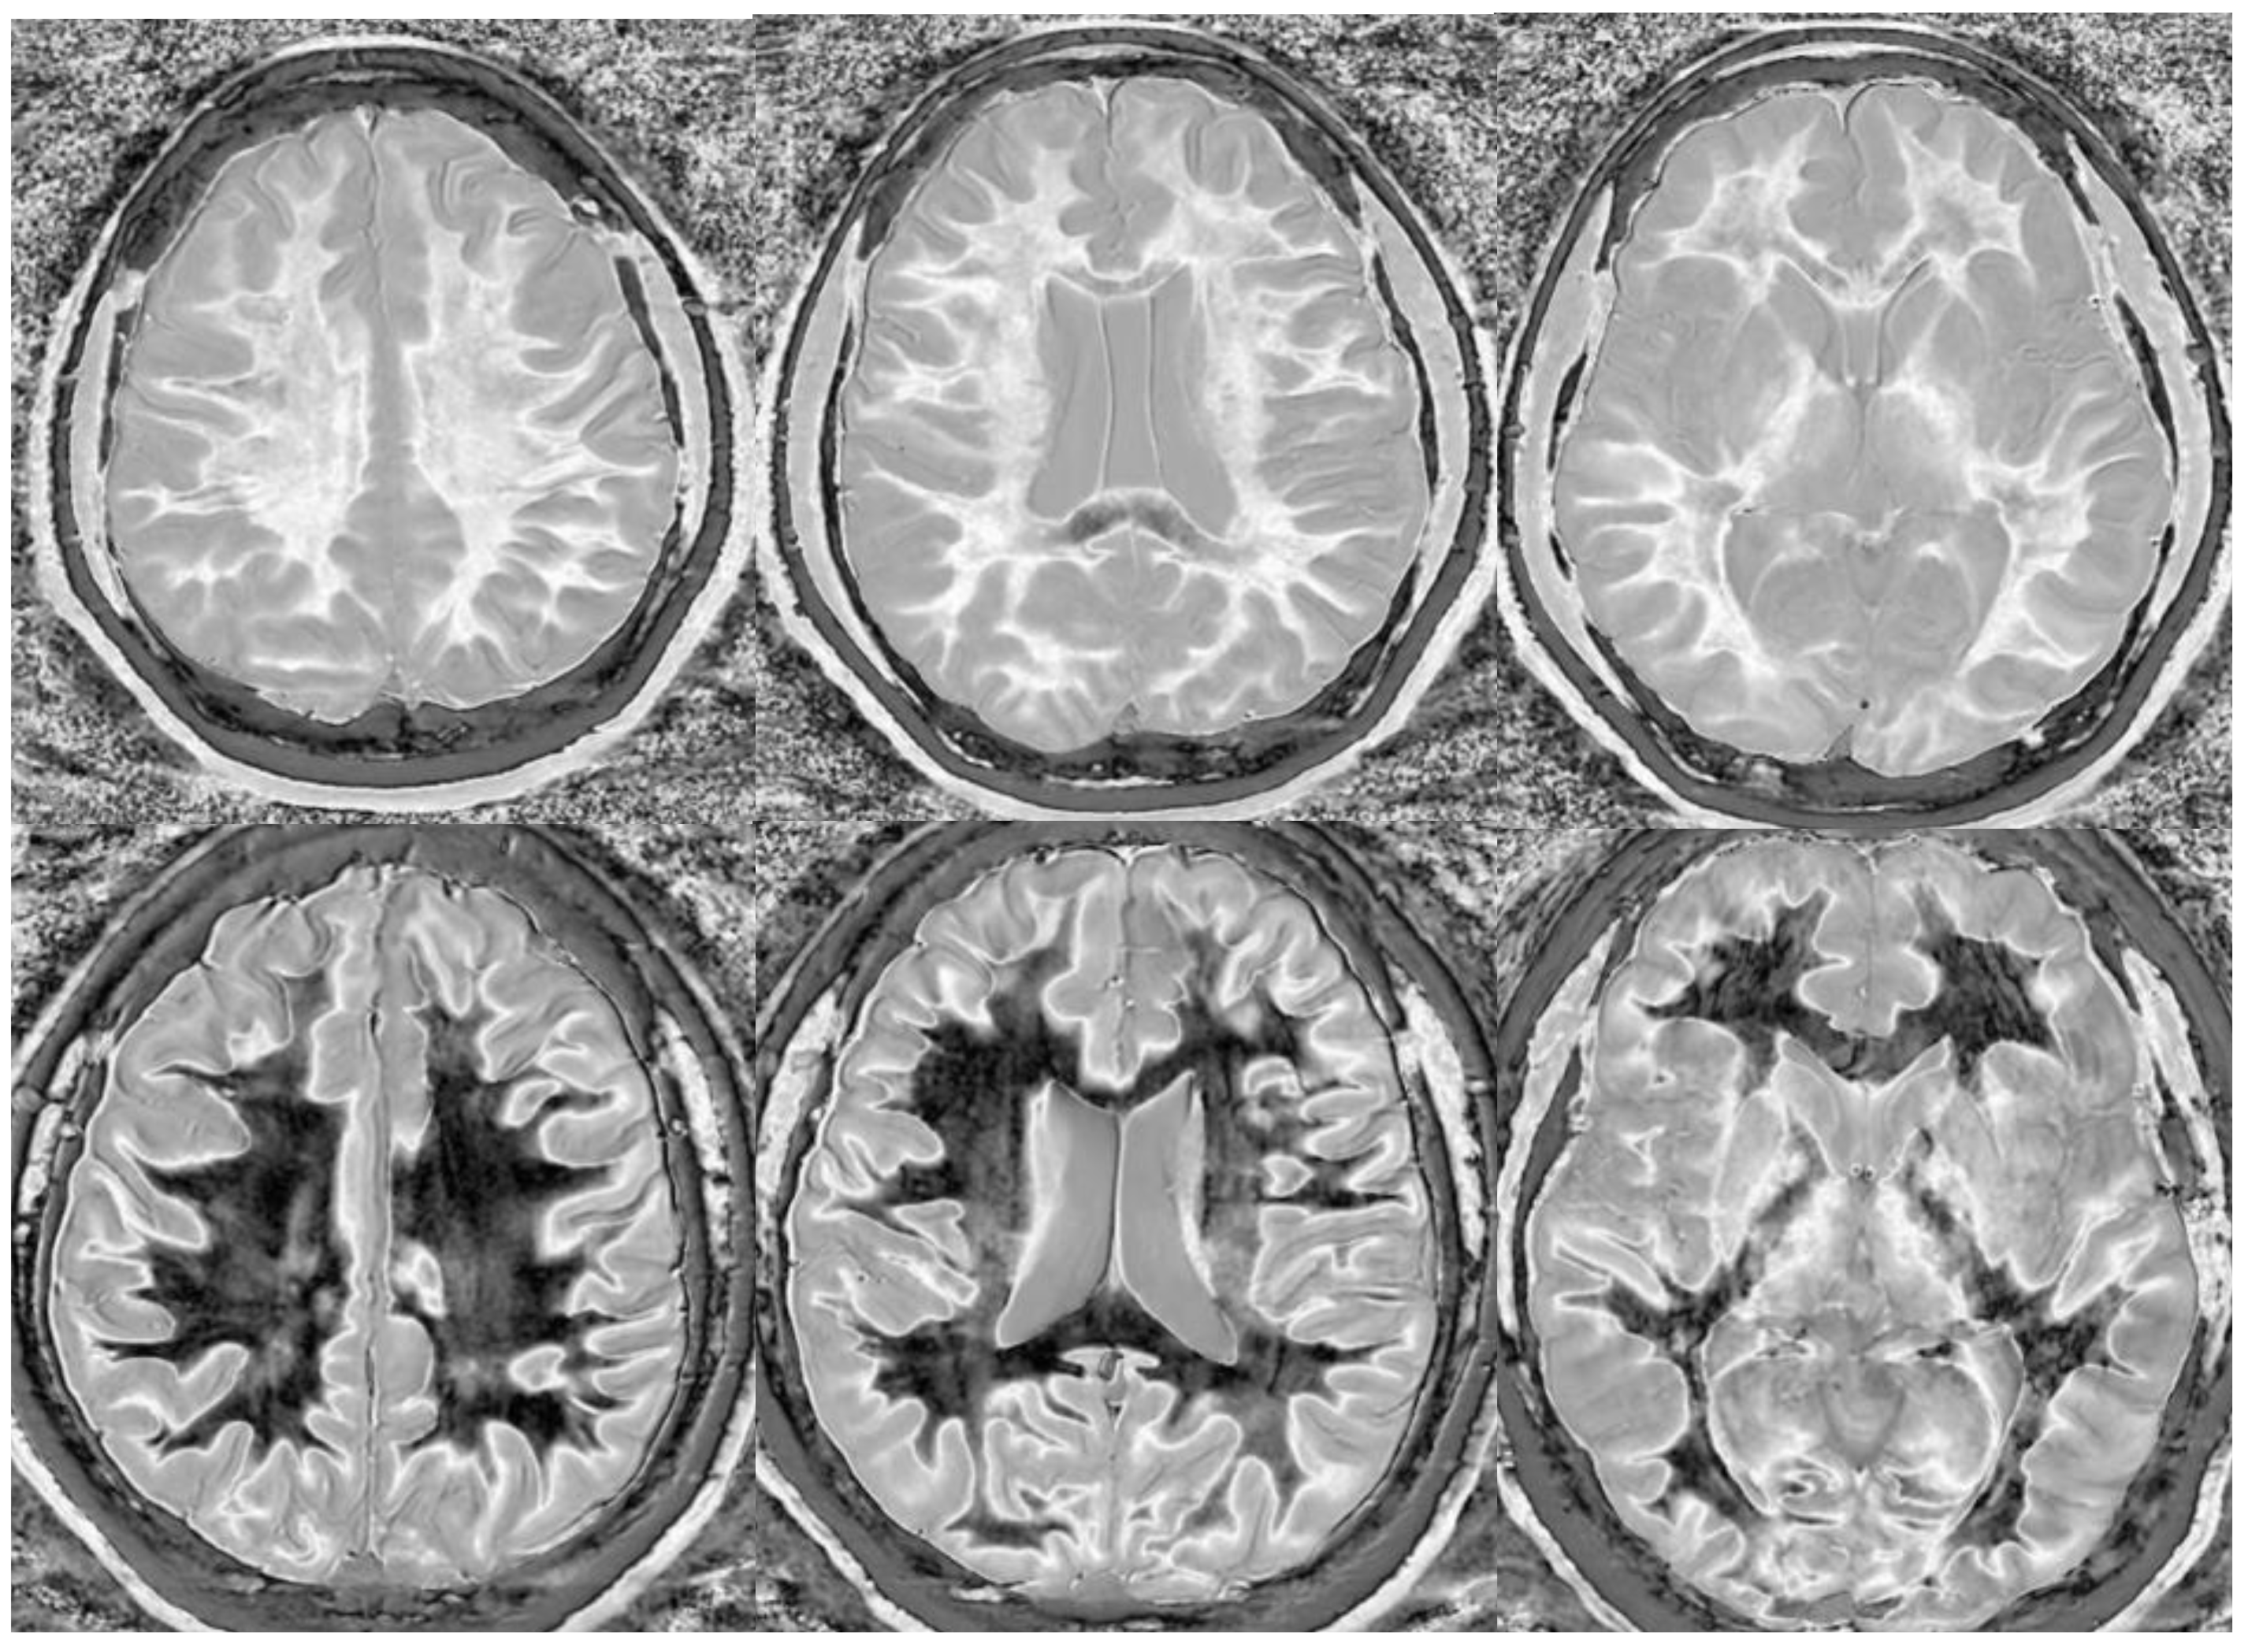

Divided Subtracted Inversion Recovery (dSIR) in a patient with multiple sclerosis (MS). Three axial narrow middle domain images in a patient with an acute MS flare at the level of the centrum semiovale (left), corona radiata (middle), and basal ganglia (right). TIshort = 350 ms. TIlong = 500 ms. TE = 7 ms, TR = 5000 ms. The white matter is not black as in Figure 9b. There is a widespread increased signal, though not a “white out” sign as described in Figure 14. This is an “intermediate” appearance but not considered normal.

We believe that dSIR is well suited to identifying generalized changes in white matter T1. We have described the “white out sign” as dSIR findings of a widespread and relatively homogeneous high signal throughout the white matter (Figure 14). This contrasts with normal, predominantly low-signal white matter. A third category of a widespread, less increased signal represents an intermediate form of the white out sign.

Figure 14.

Normal and abnormal divided Subtracted Inversion Recovery (dSIR) images. Narrow middle domain images in three patients at the level of the centrum semiovale. TIshort = 350 ms. TIlong = 500 ms. TE = 7 ms, TR = 5000 ms. The left image shows an example of the “white out sign”, with a diffusely increased signal throughout the white matter. The center image is an example of normal. The white matter has a mildly increased signal that is normal because TIshort = 350 ms nulls tissue with T1 values less than that of white matter. The image on the right has an intermediate appearance, probably abnormal but not a “white out”.

We have used dSIR to identify acute and chronic generalized white matter changes otherwise occult on clinical imaging. In two patients with suspected delayed post-hypoxic ischemic leukoencephalopathy (Grinker’s myelinopathy), dSIR demonstrated widespread increased white matter T1, despite a normal appearance of the white matter on T2-FLAIR images (Figure 15 and Figure 16) [26]. Both patients had experienced prolonged hypoxia due to attempted suicide. One was due to a drug overdose, and the other was due to asphyxia. Scans were obtained nine months and two years following injury. Grinker’s has been considered a rare disease, because conventional imaging is typically normal. The disorder may not be as rare as originally thought. dSIR could show obvious findings in symptomatic patients with previously normal conventional T2-FLAIR images.

Figure 15.

Divided Subtracted Inversion Recovery (dSIR) in a patient with Grinker’s myelinopathy. Top row: Narrow middle domain dSIR images at the level of the centrum semiovale (left), corona radiata (middle), and basal ganglia (right) in a patient with persistent symptoms following prolonged hypoxia due to a suicide attempt. TIshort = 350 ms. TIlong = 500 ms. TE = 7 ms, TR = 5000 ms. There is a diffuse “white out”. Bottom row: T2-FLAIR images at matching levels show normal-appearing white matter. Scans were obtained 9 months following injury.

Figure 16.

Divided Subtracted Inversion Recovery (dSIR) in a patient with Grinker’s myelinopathy. Top row: Narrow middle domain dSIR images at the level of the centrum semiovale (left), corona radiata (middle), and basal ganglia (right) in a patient with persistent symptoms following prolonged hypoxia due to drug overdose. TIshort = 350 ms. TIlong = 500 ms. TE = 7 ms, TR = 5000 ms. There is widespread “white out”, with some sparing in the deep frontal lobe white matter. Bottom row: T2-FLAIR images at matching levels show normal-appearing white matter. Scans were obtained 2 years following injury.